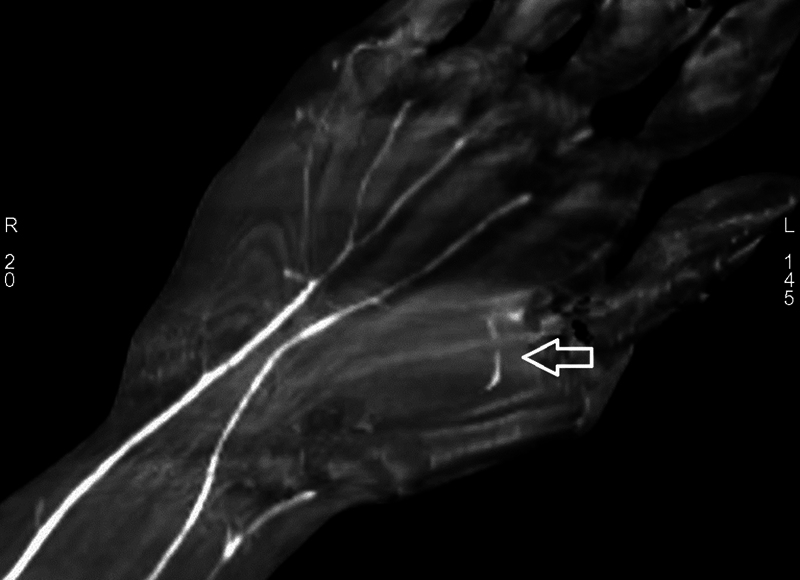

Incidental Finding of an Injured Anomalous Artery in the Forearm: To Repair or Not.